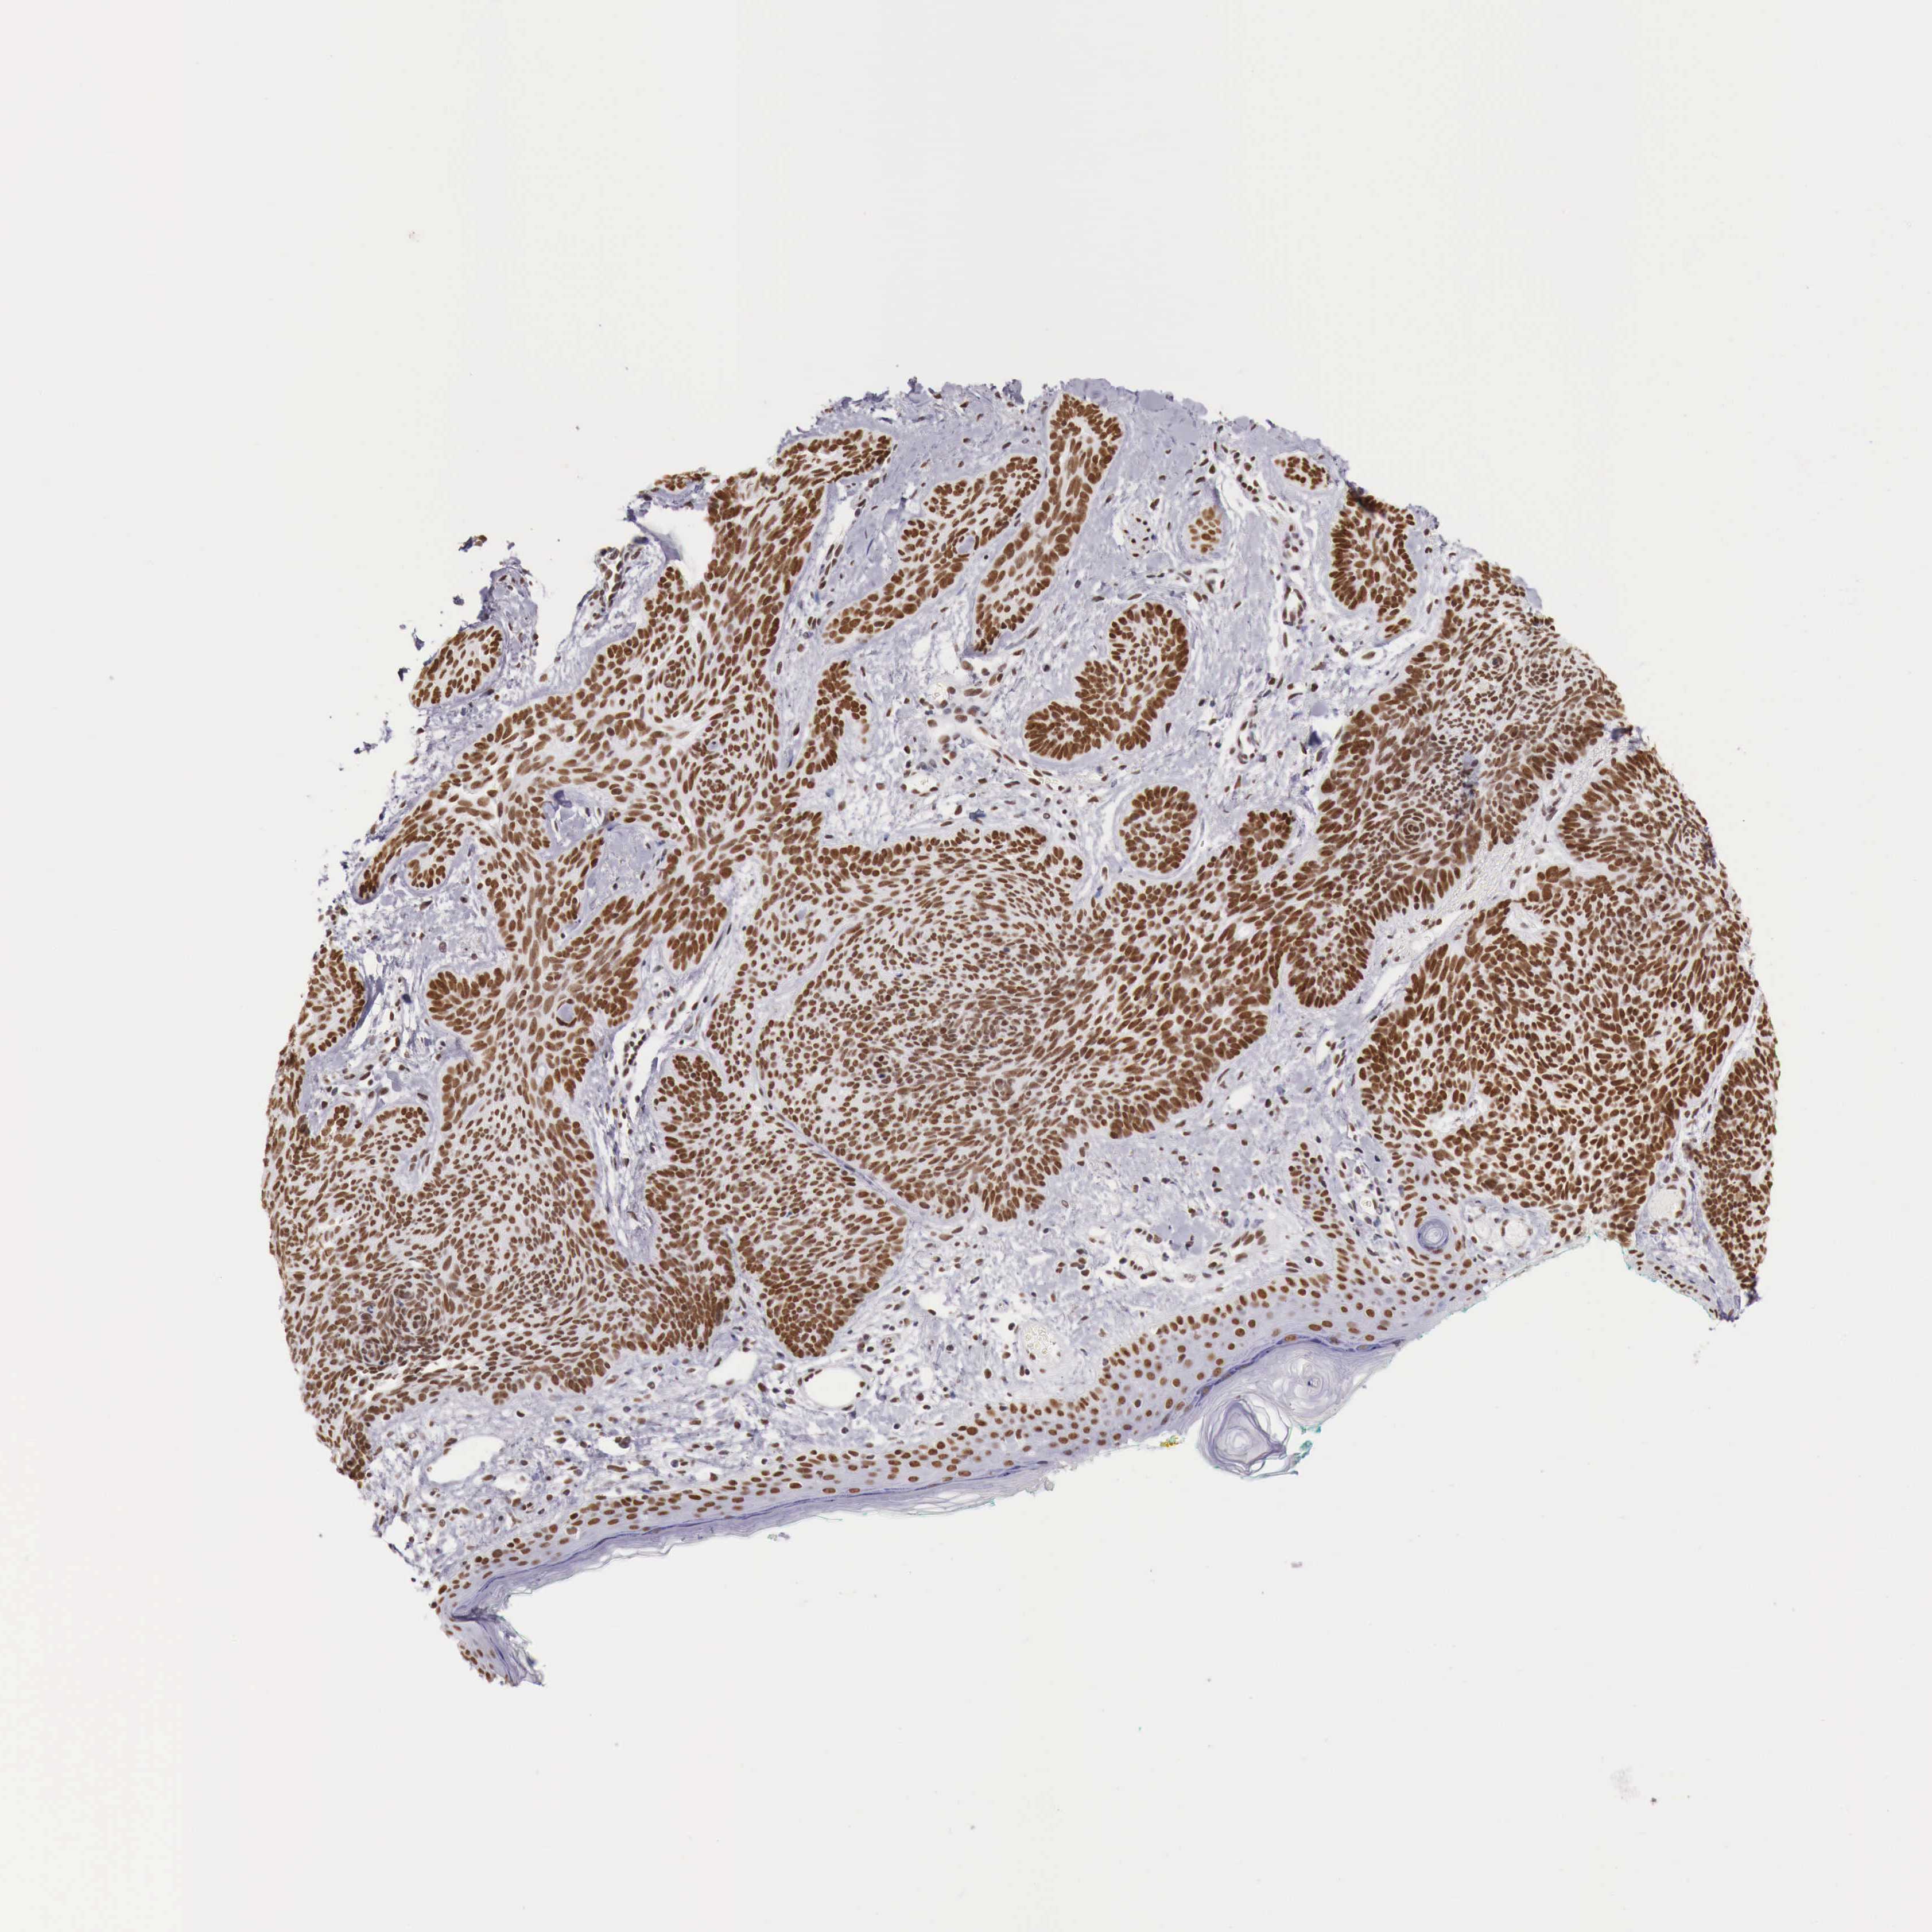

SKIN CANCER - Protein expressioni

A mouse-over function shows sample information and annotation data. Click on an image to view it in a full screen mode. Samples can be filtered based on level of antibody staining by selecting one or several of the following categories: high, medium, low and not detected. The assay and annotation is described here.

Antibody staining in the annotated cell types in the current human tissue is reported as not detected, low, medium, or high, based on conventional immunohistochemistry profiling in selected tissues. This score is based on the combination of the staining intensity and fraction of stained cells.

Each image is clickable and will lead to virtual microscopy that enables deeper exploration of all samples and also displays staining intensity scores, fraction scores and subcellular localization as well as patient and tissue information for each sample.

Antibody HPA000538

Staining

High

Intensity

Strong

Quantity

>75%

Location

Nuclear

Squamous cell carcinoma, NOS